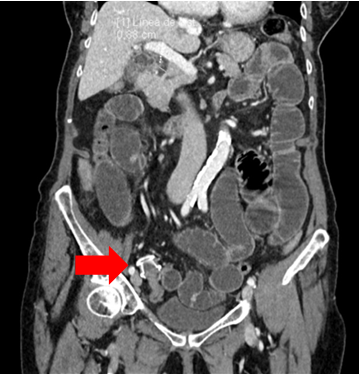

A 91-year-old woman with a history of recurrent biliary colic and chronic cholecystitis, previously treated by endoscopic endoluminal drainage with placement of an AXIOS 15-10 cholecystoduodenal prosthesis, with a good evolution after the procedure.